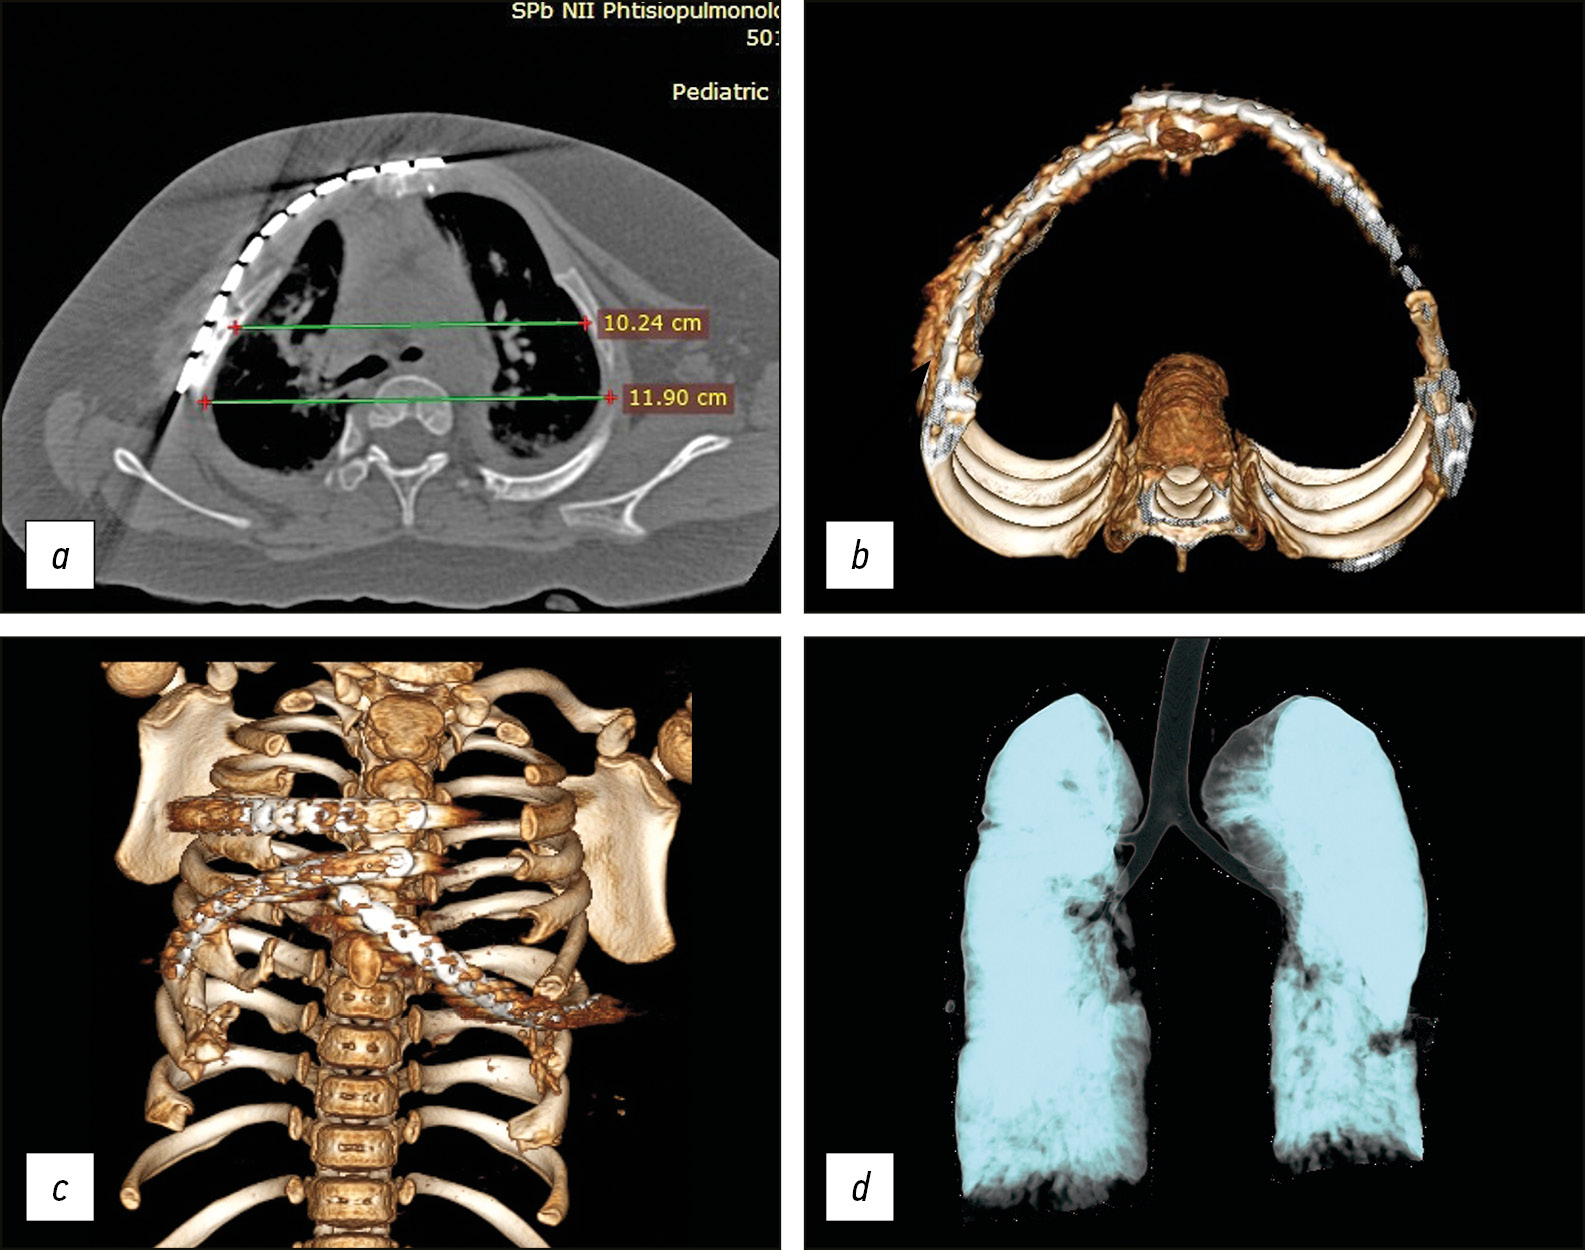

Контрольная компьютерная томография грудной клетки выполнена через 3,5 мес. после операции: грудино-реберный комплекс фиксирован пластинами и винтами. Положение металлоконструкций стабильное. Западение ребер справа устранено. Пневмоторакса, гидроторакса нет.

Лучевые данные, а также показатели, характеризующиеся увеличением линейных размеров гемитораксов и объемных показателей легких, представлены в табл. 1 и на рис. 3: увеличение показателя ИГКГК и объема правого легкого после первого этапа торакопластики составило 11,7 и 18,3 % соответственно. Объем левого легкого практически не изменился (+2,2 %).

Рис. 3. Компьютерная томограмма (а) и 3D-компьютерная реконструкция (b) после I этапа хирургического лечения: а — аксиальный срез (индекс горизонтальной компрессии грудной клетки = 71,8 %); b — правый гемиторакс имеет правильную форму (положение одной из реберных пластин отмечено стрелкой); с — 3D-мультиобъемная реконструкция

Fig. 3. Axial sections of CT scans (a) and a 3D-CAT reconstruction (b) after the I stage of surgical treatment: a-HCCI = 71.8%: the right hemithorax has the corrected shape (the position of one of the rib plates is marked with an arrow); c - 3D multi-volume lung reconstruction after the I stage of surgical treatment (See the text for the details).